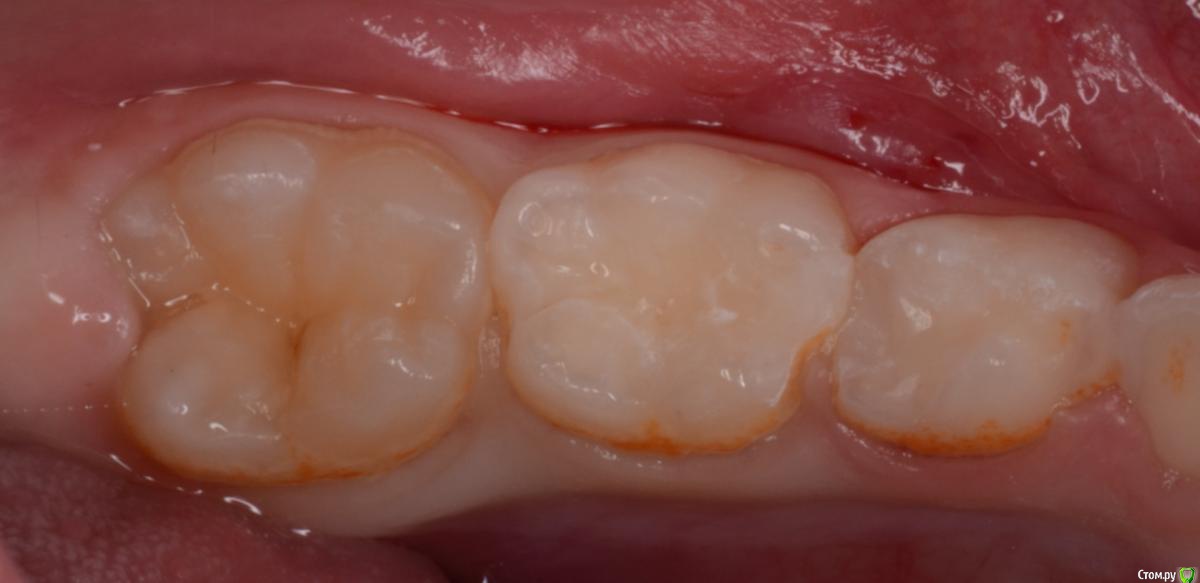

CRAZYDUCK Опубликовано 20 февраля, 2020 Автор Поделиться Опубликовано 20 февраля, 2020 Верхнее фото - зуб с герметиком . Со слов мамы перед герметизацией зуб не чистили , врач сразу нанёс герметик ( по виду похоже на жидкотекучий композит ).под жидкотекучим был кариес . Убрала жидкотекучий композит рондофлекс , препарирование и восстановление пакуемым и герметиком . 2 Ссылка на комментарий

CRAZYDUCK Опубликовано 21 февраля, 2020 Автор Поделиться Опубликовано 21 февраля, 2020 Почему-то не по порядку фото грузятся . Ребёнок 4 года , ранее был опыт лечения в наркозе , 7.5 восстановлен окклюзионно и вестибулярно , 7.4 окклюзионно . На фото «до» видно налёт в пришеечной зоне . Восстановила коронками в ЗакС 1 Ссылка на комментарий